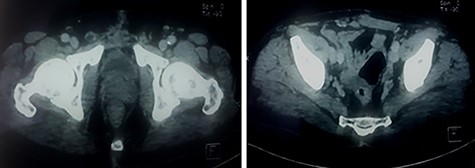

A 59-year-old patient presented at the emergency department with an acute urine retention. As a past medical history, the patient suffered from chronic hypogastric pain with LUTS and constipation over a period of 6 months. The clinical examination revealed a distended bladder that required transurethral bladder catheterization. The digital-rectal examination showed a bulging pelvic mass in the rectum, the prostate has not been palpated. The blood analysis revealed an elevation of creatinine level to 123 μmol/l with hyperleukocytosis. Prostate-specific antigen (PSA) was within normal range and urine culture was negative. Abdominal and pelvic Computed tomography (CT) scan was performed and showed a multilocular heterogeneous cystic mass in the rectovesical and supravesical spaces, measuring 13 × 10 × 9 cm, compressing the bladder and the two ureters with bilateral major upper tract dilation. The cystic mass had many septa of different thickness mildly enhancing after contrast administration (Fig. 1). There were no nodular solid enhancing components or evident signs of lymphadenopathies or metastatic lesions.

CT scan showing pelvic multilocular heterogeneous cystic mass with many septum mildly enhancing after contrast.